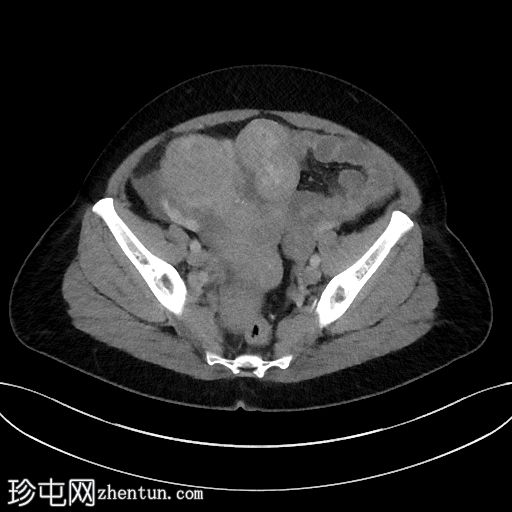

入院时CT检查

CT

1.jpg

腹部中部可见一巨大、不均匀、中心坏死的肿块。

中至大量腹水。

子宫肌瘤。